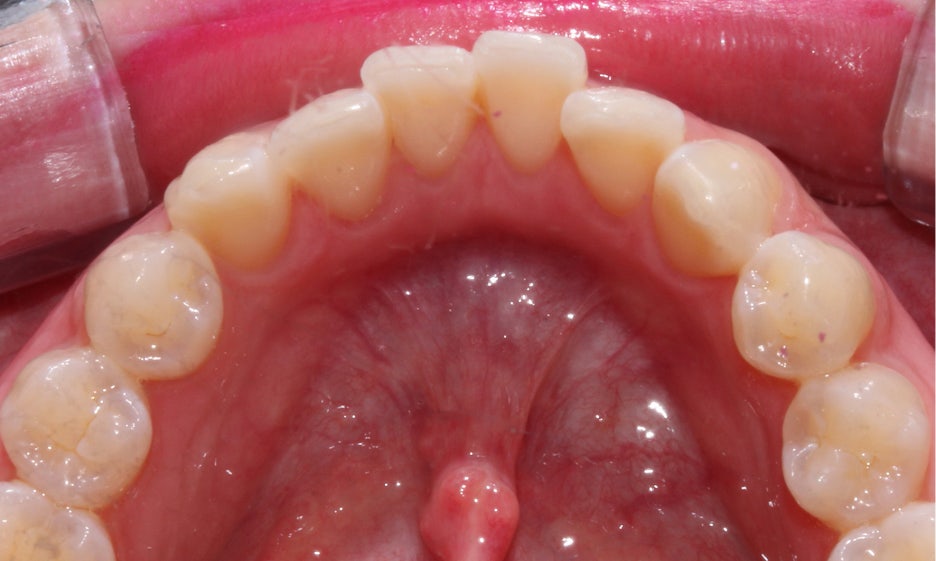

하악의 경우 상악과 마찬가지로 전치부의

crowding이 있는 모습인데요,

치아가 서로 포개어져 있는 부분이

있기 때문에 교정 후 미세하게

블랙트라이앵글이 발생할 수 있습니다.

블랙트라이앵글의 경우 정도가

심하지 않다면 치아색과 비슷한

색상의 레진으로 틈을 채울 수 있는데요,

잇몸이 퇴축된 정도가 심하고 치근이

많이 드러난 상태라면 레진보다

무삭제 라미네이트 '세라필름'을

적용하여 광범위한 빈 틈을 수복하는 것이 좋습니다.

뻐드렁니교정 후 상악 교합면을 보면

서로 겹쳐져 있던 중절치가 가지런하게

배열된 것을 확인할 수 있는데요,

전체적인 안모의 형태도 이상적인

U-라인으로 바뀌어 정돈된 느낌입니다.

하악의 경우 전치부의 Crowding으로 인해

삐뚤거렸던 치열이 가지런하게 바뀐 모습입니다.